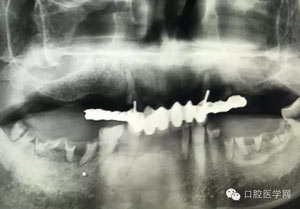

病例2:364647中齲的樹脂充填,現(xiàn)在樹脂的充填材料非常之多,有些時候,我們感覺有了好的材料我們就可以做出好的修復(fù),可是這是在我們有扎實的基本功的基礎(chǔ)上的,我們可以沒有那么好的樹脂,那么多的顏色選擇,修復(fù)的那么的逼真,但是我們至少要恢復(fù)患者牙齒的功能,將腐質(zhì)去除干凈,薄壁弱尖消除掉,選擇好適應(yīng)癥,給患者以盡可能好的修復(fù)。